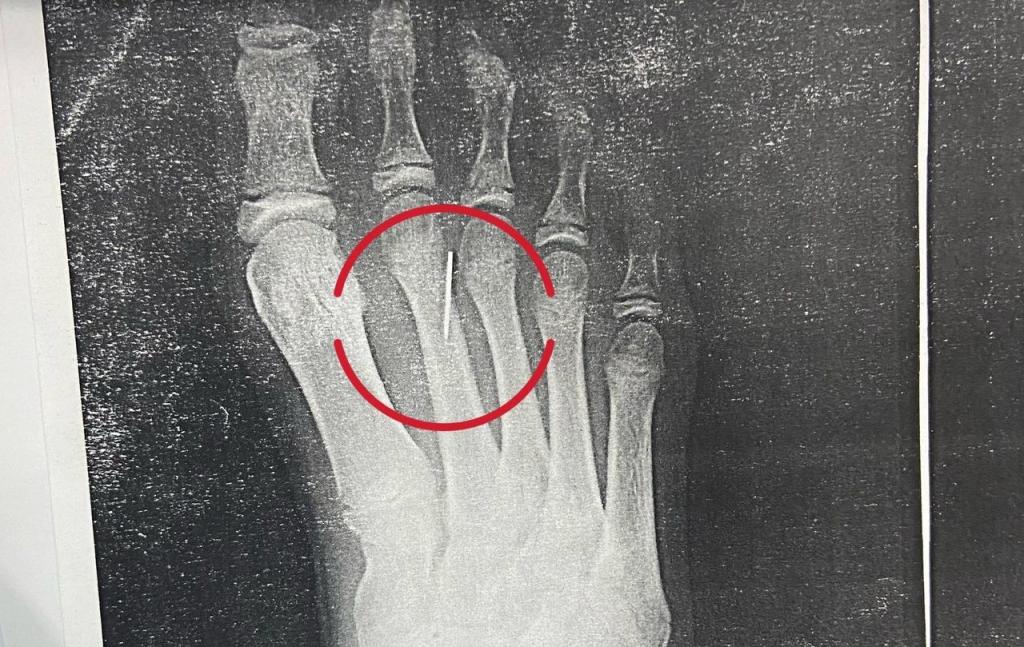

В Уфе прооперировали ребенка с иглой в ступне

В ГДКБ №17 Уфы прооперировали девочку с инородным телом в ступне. Об этом сообщили на ресурсах больницы в соцсетях.После того, как ребенок наступил на иголку, родители сразу же обратились в ЦРБ, где врачи попытались удалить иглу под общим обезболеванием, однако извлечь инородное тело не удалось.

«При помощи небольшого разреза, ориентируясь на рентгеновские снимки, мы нашли иголку и успешно удалили её. Застрявшие иголки опасны тем, что они могут нагнаиваться, мигрировать по тканям, а также, воткнувшись в кость, могут вызвать такое осложнение, как остеомиелит, то есть гнойно-некротический процесс, который может привести к летальному исходу», — рассказал травматолог-ортопед Ирек Шарипов.

Операция прошло успешно, пациентка чувствует себя хорошо и идет на поправку. Теги: